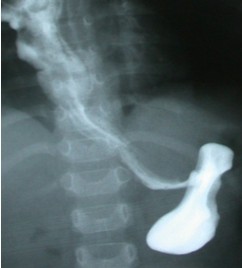

气管食管瘘(tracheoesophageal fistula)系由于先天性胚胎发育异常形成气管与食管间由瘘道相连通所致病。

常见气管食管瘘伴食管闭锁,气管发育不全,并有瘘管与食管相通,食管或呈盲端状闭锁,扩大呈囊状,亦见气管-食管瘘不伴食管闭锁,少数病例由支气管与食管相通,形成支气管-食管瘘。